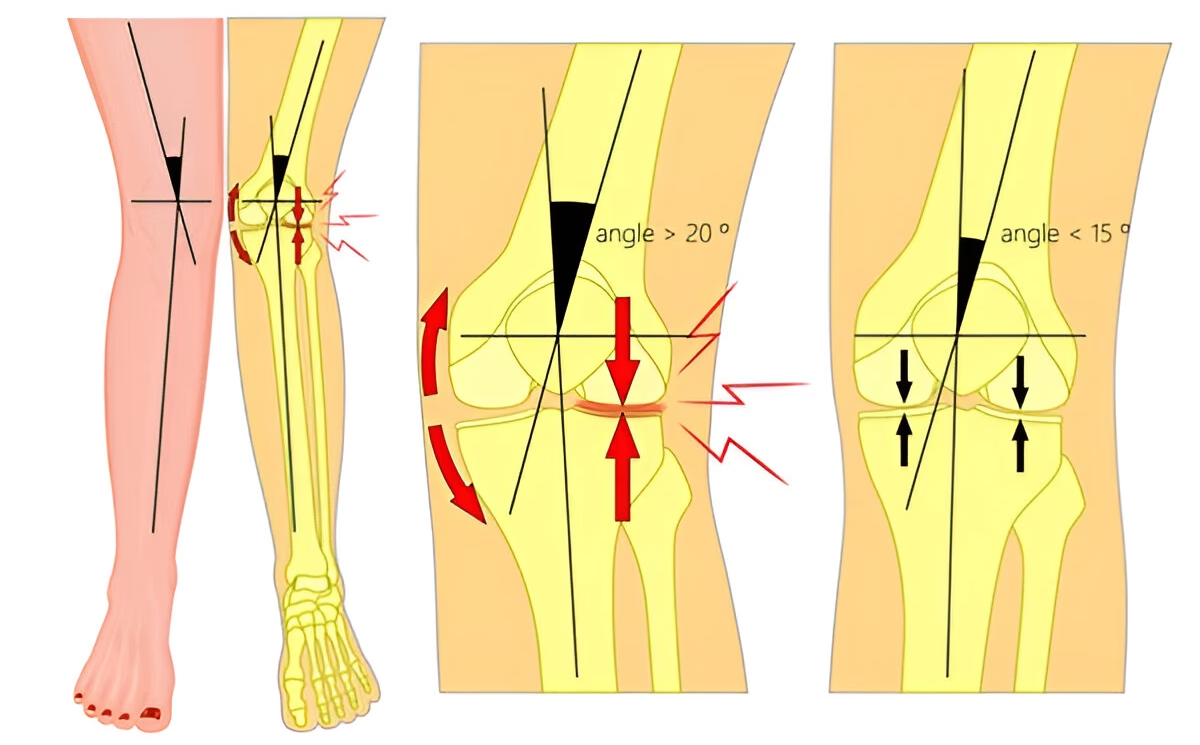

- Ángulo de las Rodillas y Distancia Intermaleolar: Con las rodillas juntas, la distancia entre los tobillos (intermaleolar) no debe ser superior a 8 cm. Una distancia mayor sugiere un valgo más pronunciado.

- Eje de Carga: Es crucial evaluar si el eje de carga que va desde la cadera hasta el tobillo pasa a través del centro de la rodilla. Si este eje se desvía por fuera de la rodilla, indica una distribución anormal del peso que puede generar estrés en la articulación.

Cuando el Genu Valgo sobrepasa los valores considerados normales, especialmente si existe alguna enfermedad ósea subyacente como las mencionadas anteriormente, la cirugía correctora puede estar indicada. El objetivo principal del tratamiento quirúrgico es aprovechar el crecimiento residual del niño para alinear gradualmente el deseje en valgo, es decir, corregir la angulación de las rodillas.

Uno de los procedimientos quirúrgicos más comunes y efectivos para corregir el Genu Valgo en niños que aún están en crecimiento es la Hemiepifisiodesis. Esta técnica mínimamente invasiva consiste en cerrar temporalmente el cartílago de crecimiento de la rodilla, pero solo de un lado (el lado interno del fémur o la tibia, dependiendo de la deformidad específica). Al detener temporalmente el crecimiento en el lado interno, el lado externo de la rodilla sigue creciendo de forma asimétrica. Con el tiempo, esta diferencia en el crecimiento permite que la pierna se enderece gradualmente y corrija el defecto en valgo.

Consideremos el caso de una niña de 12 años con un valgo fémoro-tibial superior a 10 grados y una distancia intermaleolar (entre los tobillos) superior a 10 cm. Ambas medidas indican un Genu Valgo significativo y fuera de los parámetros normales para su edad. Se le realizó una Hemiepifisiodesis. Catorce meses después de la cirugía, se observó una corrección exitosa de la deformidad, lo que le permitió recuperar una marcha normal y reducir el riesgo de problemas articulares a largo plazo.